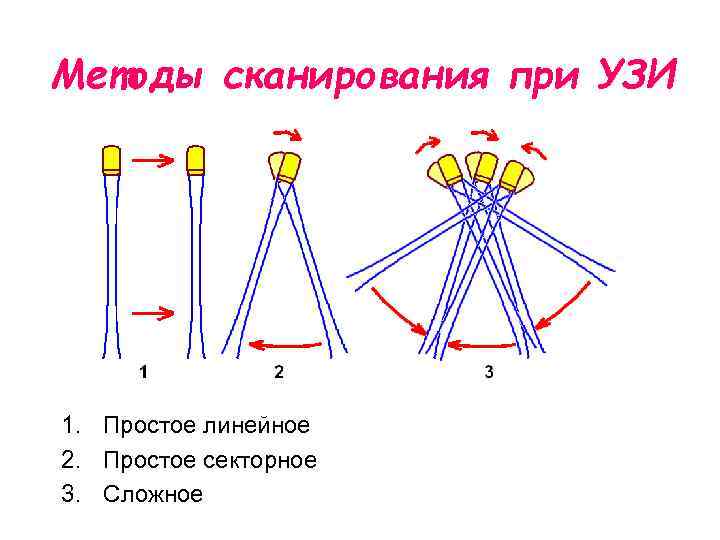

Методы сканирования при УЗИ 1. Простое линейное 2. Простое секторное 3. Сложное

Методы сканирования при УЗИ 1. Простое линейное 2. Простое секторное 3. Сложное